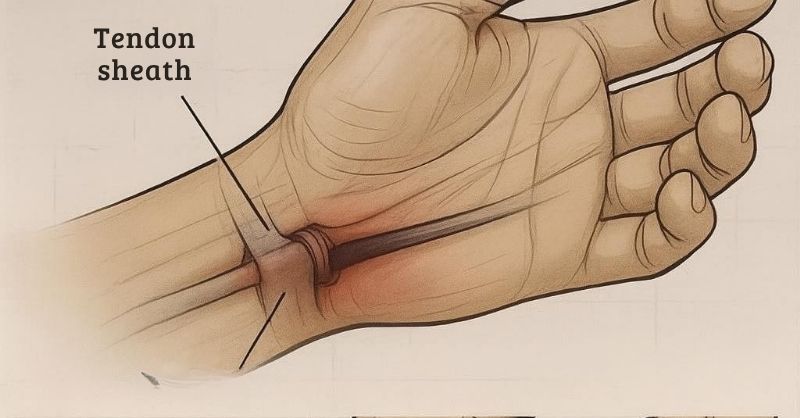

Why Do Hands and Feet Go Numb? Common Causes and Natural Solutions

Have you ever felt tingling, numbness, or a crawling sensation in your hands or feet? This condition, medically known as paresthesia, can sometimes be temporary and harmless. However,...